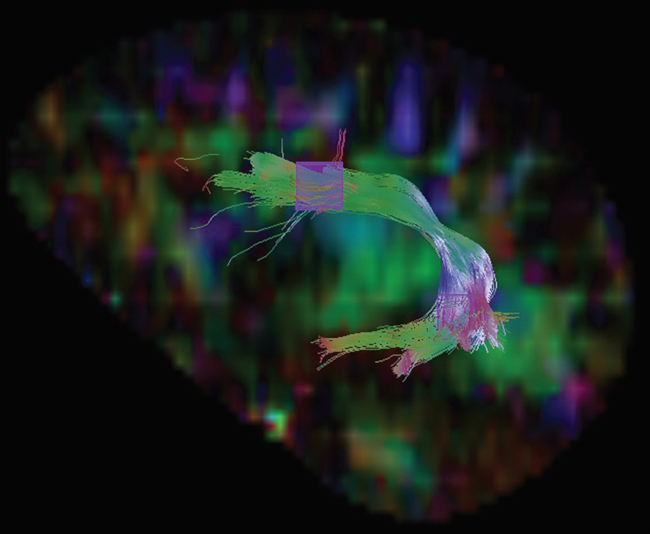

La distribución anatómica de este tracto va en dirección del lóbulo frontal inferior, pasando sus fibras por el parietal, y termina en el temporal superior. En la región frontal anterior confluye junto con el FU y FFOI, haciendo difícil su aislamiento en esa zona, por lo que su siembra se realizó más posterior en su recorrido frontal. Usando el mapa de anisotropía en corte coronal como referencia para determinar la direccionalidad de las fibras, se realizaron las siembras del FLS en dos ROI. En la ►Figura 1, se muestra este fascículo en corte sagital para una mejor apreciación de su recorrido.

FLS izquierdo sobre un fondo de mapa de AF en corte sagital. Con la técnica cuboide se hizo la siembra en dos ROI, el primero en la región frontal y el segundo en la región temporal.